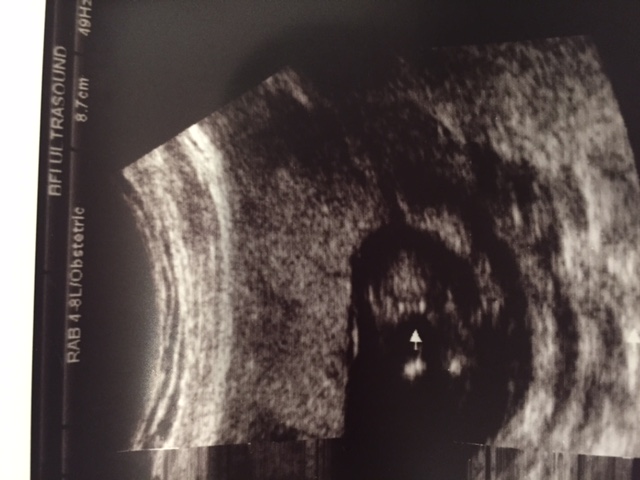

I've always heard 3 lines is a strong sign of a girl but what about 4 lines? Please help!!!

That's a girl.

looks like a girl

Girl!

Its the actual "nub" receding into the folds that will eventually be the outer labia. Shes just forming still. examples here:Embryo Development external genital sex organs - angle of the dangle boy or girl ultrasound gender scan - Baby2see

Inner thighs, labia